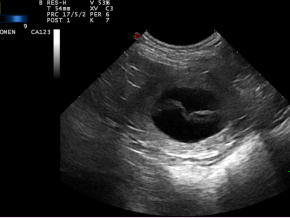

Wir freuen uns auf meine Welpen, der heutige Ultraschall war positiv